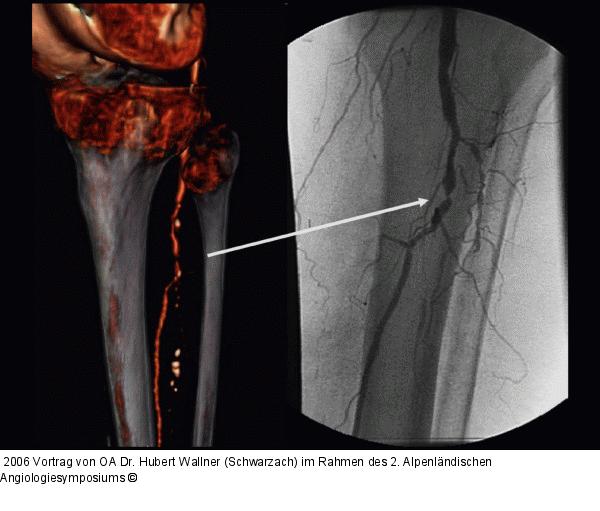

Abbildung 36: Kritische Beinischämie